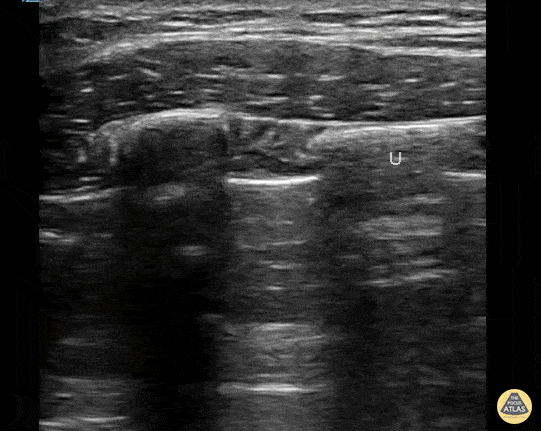

16 year old with a spontaneous pneumothorax. Serratus anterior block performed prior to chest tube placement. Not needle coming from the left under serratus muscle and above rib. Contributor: Paul Khalil, MD Nicklaus Children's Hospital @khalil3paul